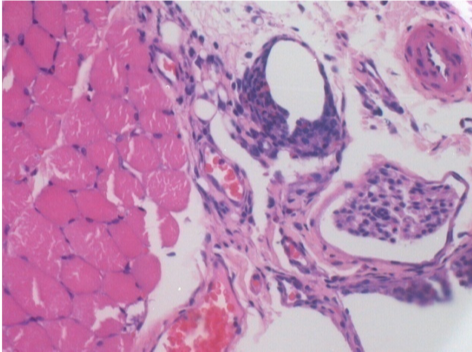

7 ay (D210) Endopeel IM Enjeksiyonundan sonra sağ pretibial kasta 0,1 ml.

7 ay sonra Restitutio reklam entegrasyonunu tamamlayın

Endopeel, yaklaşık olarak 1 aylık bir periyotta seçici bir geri dönüşümlü miyofibroliz ve inflamatuar reaksiyonu indükler.

Kas değişiklikleri neredeyse tam olarak geri döndürülebilir

Çalışmanın her yerinde nekroz veya apse bulunmadı.